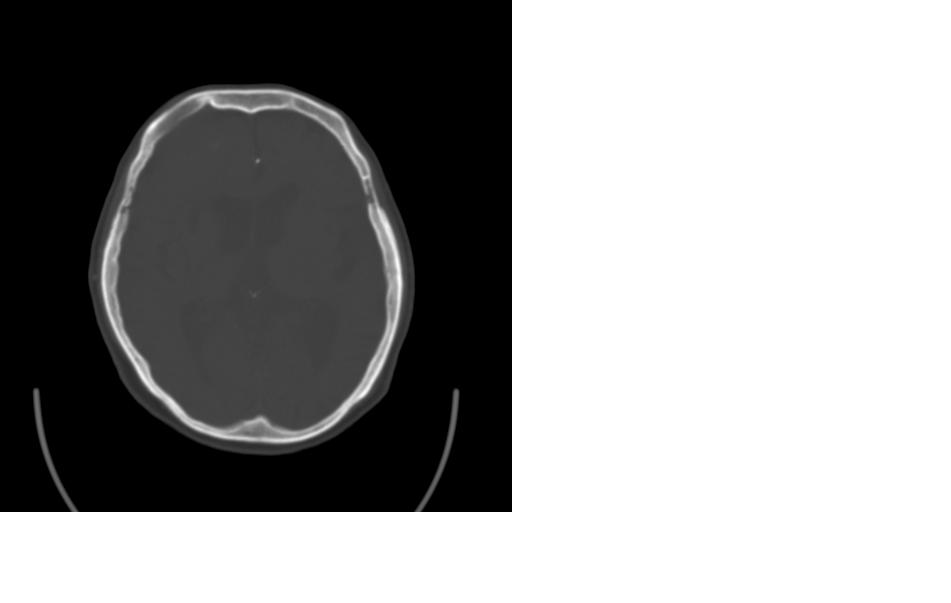

女,77岁,渐进性突眼2年,无其他明显症状

病变位于起源于右侧筛窦,右侧眼球受压移位,右侧大脑半球额叶白质受压塌陷,水肿不明显.额骨呈压迫性骨质吸收变薄.考虑脑膜瘤,建议增强吧

右侧额部软组织密度肿块,界限不清,明显向前下方增长,占位效应明显,内见钙化,局部颅骨明显吸收.考虑:右额叶脑膜瘤.建议:增强

右额窦粘液囊肿,向前累及筛窦并进入眼眶使眼球前突;向下进入颅内右额叶脑质及侧脑室受压

病变应起源于右侧额窦/或额骨板障,肿块周围骨包壳尚完整,呈膨胀挤压改变,右侧眼球受压移位,右侧大脑半球额叶白质受压塌陷,水肿不明显.考虑为良性病变,骨纤维瘤/或骨嗜酸性肉芽肿? 建议增强吧

支持:病变的起源我乐意定在右额窦。右额窦粘液囊肿或粘液腺癌累及筛窦、眼眶使眼球前突;向下进入颅内右额叶脑质及侧脑室受压变形。

右侧筛窦类圆形实质性肿块向颅内呈膨胀性生长,边缘较为光滑,其内似见囊性低密度影,边缘骨壁受压变薄移位,部分骨质缺损破坏

额骨右侧呈明显膨胀性骨质破坏,内外板明显变薄.考虑骨巨细胞瘤或动脉瘤样骨囊肿的可能性大。

定位:来源右额窦。定性:良性占位—额窦黏液囊肿。理由1、病灶中心位于右额窦区,侵及筛窦并向下向前压迫眼球2、骨质呈膨胀性改变,骨质弓形变薄但骨壳完整,如为恶性骨质应为侵蚀性破坏3、黏液囊肿好发于筛窦、额窦。